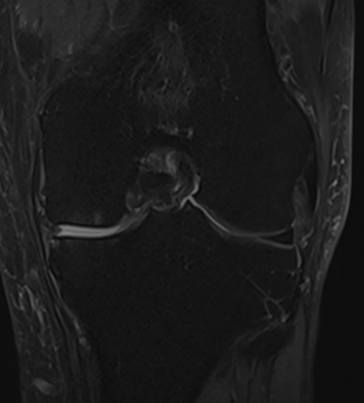

MRI scans illustrating the improvements regarding Group 2 are presented below, showing pre-treatment images with evident cartilage defects, pronounced bone marrow edema, and synovial inflammation, followed by post-treatment scans demonstrating improved joint structure, reduced edema, and decreased inflammation (Figures 12-29).

MRIs of Group 2

MRIs of Group 1

To provide a comparative perspective, additional MRI scans from Group 1 are shown subsequently. While patients in this group also displayed reductions in bone marrow edema, effusion, and synovitis, the improvements appeared less pronounced than those seen with the combined therapy. Pre-treatment MRI scans revealed extensive edema and synovial inflammation, which were partially reduced at the 2-month follow-up. However, residual joint effusion and subtle signs of inflammation remained present in some cases. These findings further support the potential benefit of combining the ChondroFiller® liquid with MSC therapy to achieve more comprehensive structural improvements and facilitate enhanced cartilage regeneration (Figures 30-41).